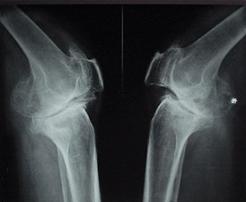

1疼痛的特點:膝骨性關節炎的疼痛,常常不知從何時開始,有時有好轉,有時增重,夜間也會疼痛,夜間膝關節伸直時疼痛加重,走路時疼痛,甚至完全不能走路。尤其是下坡下樓梯時,疼痛加重。

2疼痛的部位:膝的內側最多見,前側也有,有時後側也疼痛。外側疼痛的比較少。自覺的部位與壓疼的部位是一致的。

3運動疼走路時疼痛,休息能夠減輕。

4體位下蹲時疼痛加重,膝關節伸直時疼痛加重。

5大小便時不能下蹲,當站起時,疼痛加重,並感到膝關節內有咔嚓咔嚓的響聲。